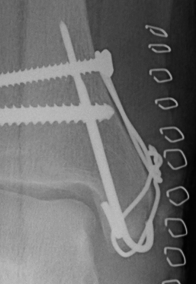

Fixation options

| Screw fixation | Tension band wire | Buttress plate |

|---|---|---|

| Type C: transverse fractures |

Type B: too small for two screws |

Type D: Vertical fractures |

Tension band wire

AO surgery reference medial malleolus cerclage wire